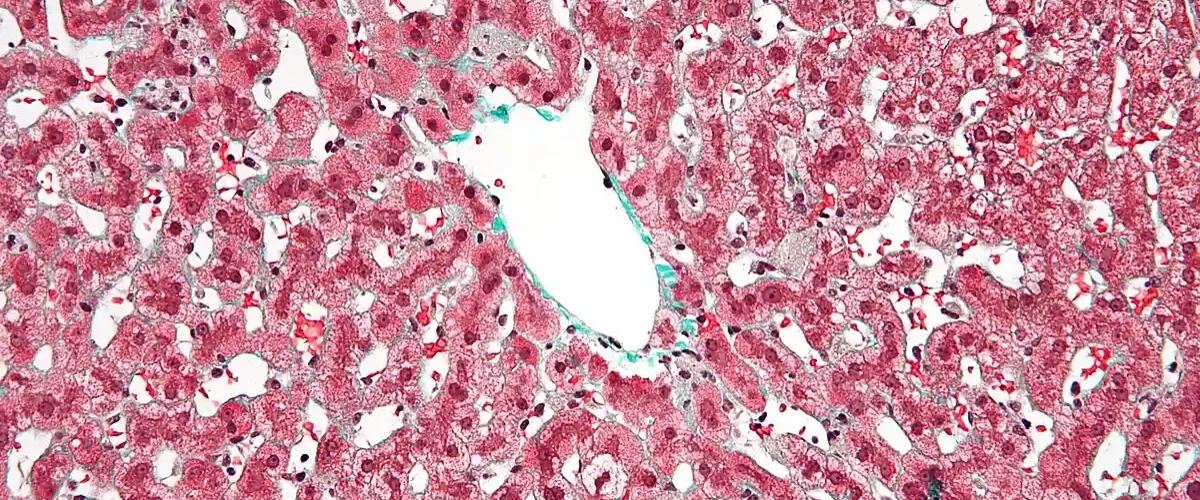

До сих пор ученые исследовали гендерные различия только на этапе фиброза печени, изучая роль половых гормонов на ранней стадии прогрессирования заболевания. Новая работа команды из Испании восполнила пробел в отношении цирроза и установила, что пол определяет скорость развития заболевания.

Эксперименты на мышах показали: у самцов осложнение цирроза — асцит — возникало по ожидаемого сценарию. У самок все было по-другому. Только увеличение дозировки токсичного вещества, провоцировавшего асцит, приводило к аналогичным повреждениям, но процесс все равно занимал примерно в два раза больше времени.